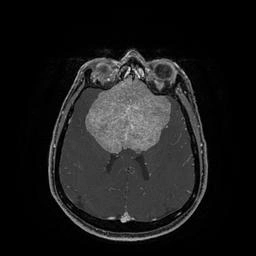

Врачи нашли менингиому диаметром в 8,5 сантиметра, которая сильно сдавливала лобные доли. Настолько большие опухоли встречаются очень редко. Кроме того, по поверхности новообразования и частично в ее капсуле проходили крупные магистральные артерии головного мозга.

Так выглядела опухоль